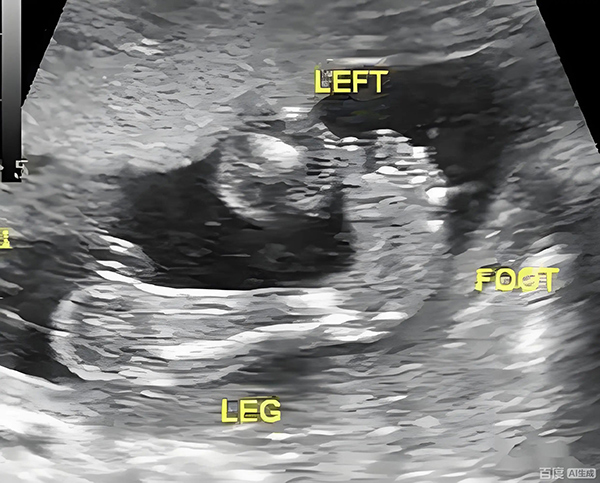

胎儿足内翻,医学上称为“先天性马蹄内翻足”,是胎儿足部发育异常导致的畸形,表现为足部跖屈(脚尖朝下)、前足内收、足跟内翻,外观类似“马蹄”。

这种情况在孕期超声中的检出率约为1‰-3‰,成因复杂:可能是遗传因素(家族史阳性风险升高)、胚胎发育过程中足部肌腱/韧带异常牵拉,也可能是子宫内空间拥挤(如双胎、羊水过少)导致的暂时性压迫。关键区别在于“孤立性足内翻”和“合并其他异常的足内翻”,两者预后差异极大。